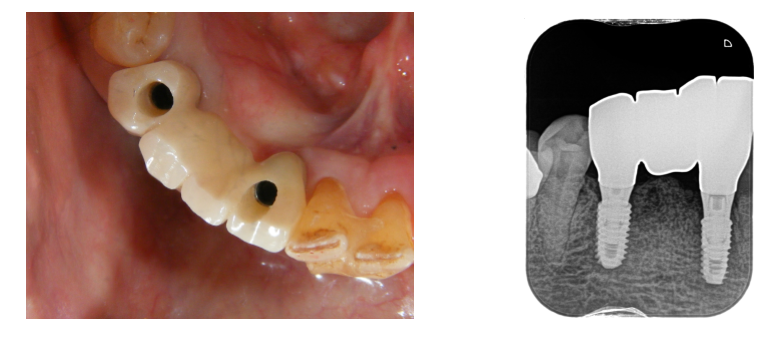

写真は鏡にのせて撮ったものです。

骨とインプラントが結合するのを2ヶ月待って歯型を採り、

上部構造を作ります。

ネジで固定するシステムです。

ネジで固定します。

前歯はネジ穴が見えないところになるように埋め込みしています。

ネジ穴を白い詰め物でふさいで完成です。